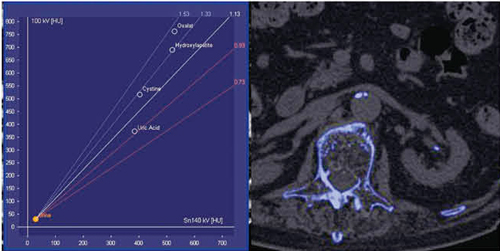

●Dual Energy

syngo.viaのDual Energyは,Two-material decompositionやThree-material decompositionの解析を,ワークステーションではなく読影端末上で行えることが特長である。図8は,腎結石に対するTwo-material decomposition解析であるが,石灰化結石を青く表示させている。また,Three-material decomposition解析のLiver VNC(Virtual Non-Contrast)では,仮想的非造影画像の作成や,Iodine mapの作成などが可能である(図9)。これらの処理が,ワークステーションではなく読影端末で可能になったことが大きなメリットである。

図8 syngo Dual Energy

Two-material decomposition解析